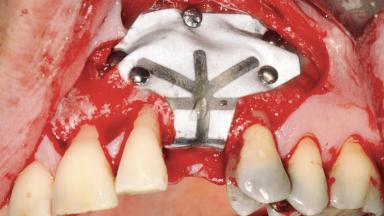

Guided Bone Regeneration (GBR) with a Particulated Autologous Graft and a ePTFE-Reinforced Membrane for Vertical Augmentation of a Single-Tooth Edentulous Space in the Esthetic Zone

Bone Augmentation Staged|Vertical

Augmentation Materials Autogenous chips|Membrane